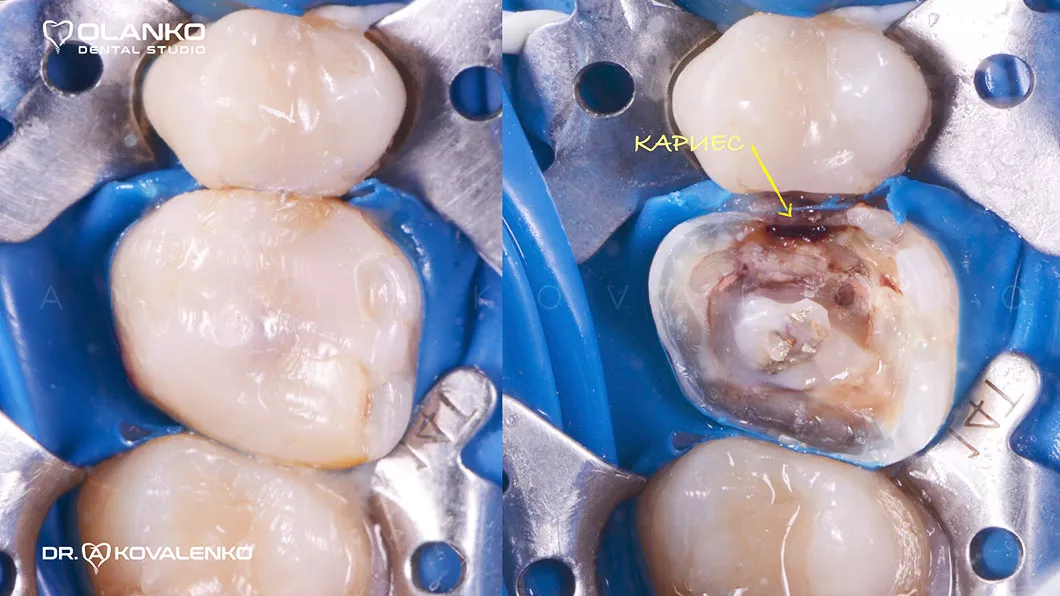

Лечение корневых каналов зуба с использованием микроскопа, на сегодняшний день, является золотым стандартом мировой стоматологической практики. Сложная система корневых каналов в зубе имеет очень малый диаметр и индивидуальную анатомию, поэтому врач, работающий без увеличения, не может качественно очистить и найти все корневые каналы на ощупь.

На примере перелечивания корневых каналов верхнего жевательного зуба

Мы имеем огромный клинический опыт лечения зубов со сложной анатомией (искривлёнными, склерозированными каналами), а также повторного перелечивания каналов с кистами, гранулемами, сломанными инструментами, с последующими отличными результатами заживления очагов хронического воспаления.